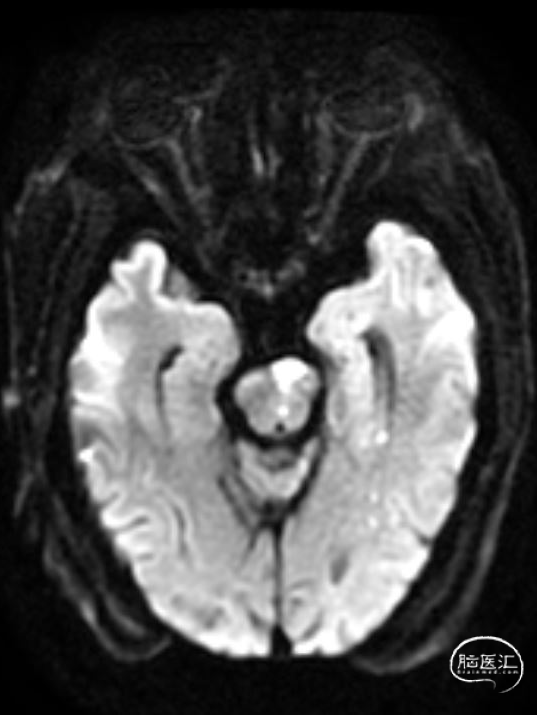

➢2023年10月28日

头颅MRI平扫:脑桥急性脑梗死,基底动脉近端重度狭窄。

➢2023年10月31日

头颅MRI平扫:脑桥、左侧小脑半球、颞叶多发急性/亚急性脑梗死。

➢2023年11月06日

头颅MRI平扫:脑桥、左侧中脑、左侧桥臂急性脑梗死。

➢2023年11月13日

头颈部CTA:头颈部动脉粥样硬化,右侧椎动脉颅内段及两侧大脑后动脉重度狭窄,基底动脉闭塞。

➢2023年11月14日

头颅MRI平扫+HRMRI:脑桥、中脑急性/亚急性脑梗死;双侧桥臂变性。

HRMRI:基底动脉闭塞并斑块合并局部出血;左侧大脑后动脉P1段斑块形成,相应管腔闭塞,左侧椎动脉V2-V4段斑块形成,相应管腔中重度狭窄,左侧椎动脉V4段管壁弥漫性增厚,相应管腔中度狭窄;右侧大脑后动脉纤细。